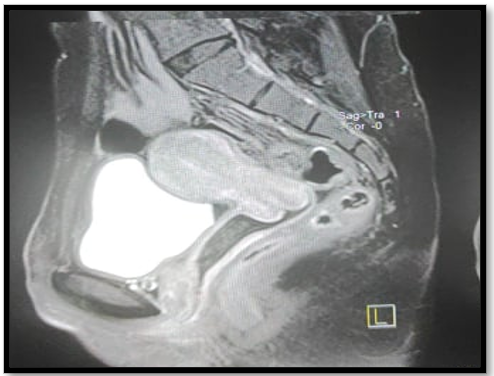

Pelvic MRI: no abnormalities (figure 2).

Figure 2: IRM pelvienne sans anomalie